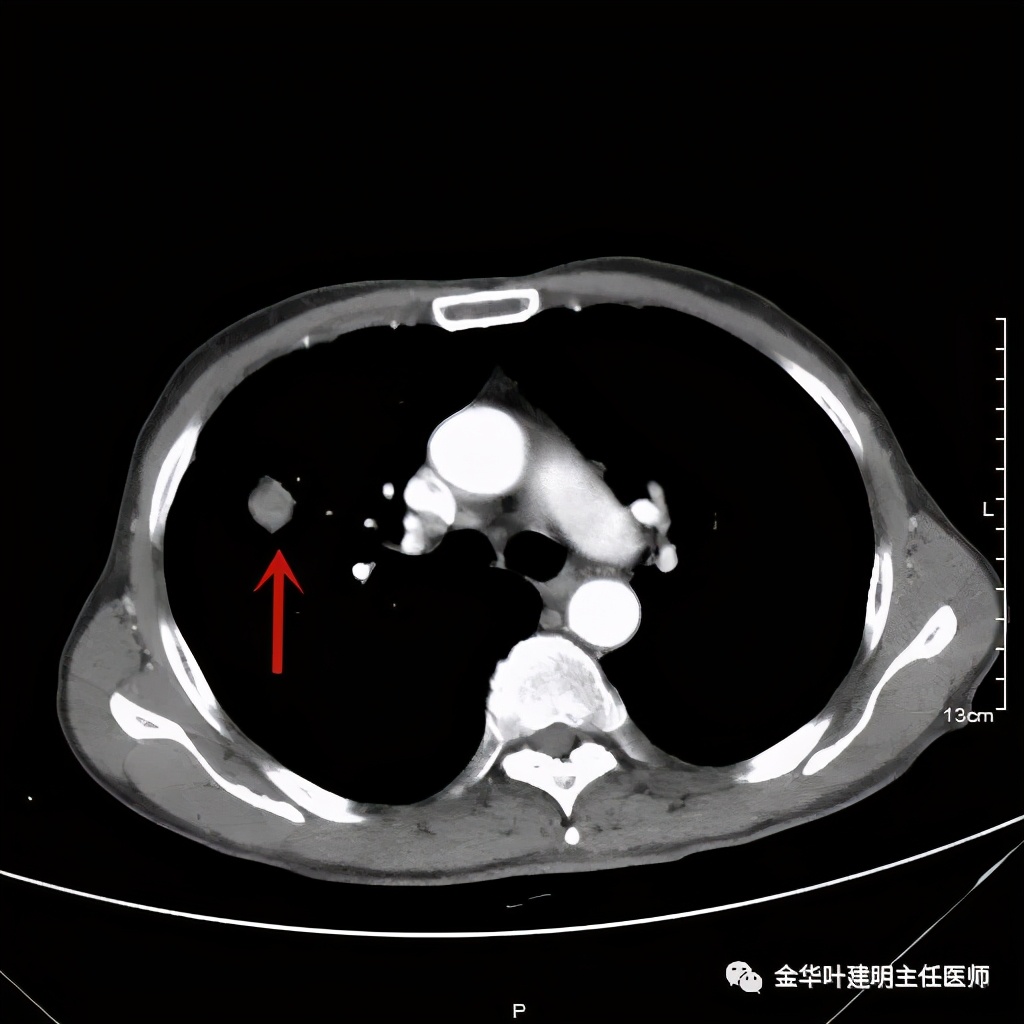

金华的某A,今年73岁,男性。检查发现右上肺占位,肿瘤筛查指标正常,血常规与CRP正常,临床有反复咳嗽、咳痰2年余(考虑慢支的关系,近期也许同时有病灶的影响)。一年前还在外院做过支气管镜,也未见确切异常。我们先来看他这次的胸部CT图像:

上图示病灶